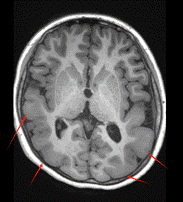

图为9岁女孩,双侧后头部巨脑回畸形,成串痉挛发作,胼胝体切开术后无发作

3.代谢与免疫机制:被忽视的“幕后推手”